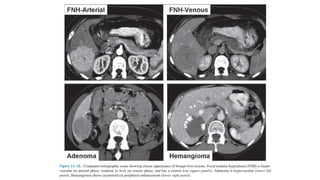

Multiphasic Contrast Computerised

Tomography

• Liver has dual blood supply

• Normal parenchyma is supplied for 80% by the portal vein and only for 20%

by the hepatic artery

• All liver tumors get 100% of their blood supply from the hepatic artery

• In Arterial phase

• hypervascular tumors will enhance via the hepatic artery

• normal liver parenchyma does not yet enhances (because contrast is not yet

in the portal venous system)

• Hypervascular tumors will enhance optimally at 35 sec after contrast injection

• Portal venous phase

• To detect hypovascular tumors

• Scanning is at about 75 seconds

• Delayed Phase

• Begins at about 3-4 minutes after contrast injection

• Imaging is best done at 10 minutes

• Washout of contrast – HCC

• Retention of contrast – heamangioma

• Retention of contrast in fibrous tissue

• Capsule of HCC

• Central scar of FNH